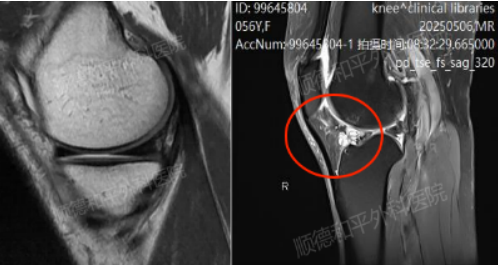

骨科一区吴建伟主任接诊后,立即结合外院检查结果进行详细评估,并为其安排了进一步的核磁摄片检查,结果显示,梁姐的右膝关节已出现严重退行性病变:骨质增生、关节面软骨磨损变薄、腔骨上端关节面下骨损伤及小囊肿。

更棘手的是,外侧半月板撕裂,内侧半月板前后角变性,前交叉韧带损伤水肿,关节周围软组织肿胀伴大量积液。这些复杂的病情是导致患者膝盖疼痛难忍,行动受到极大限制的综合原因。

正常半月板&损伤异常半月板摄片对比